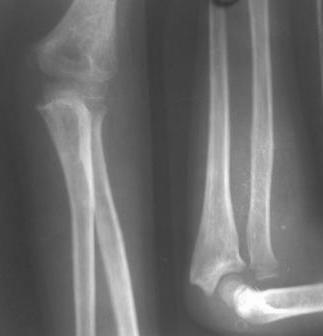

Иллюстрация к лечению застарелого повреждения Монтеджиа

Пациентка клиники детской травматологии ЦИТО

На рентненграмме видна деформация локтевой кости на границе верхней и средней трети. Ведь там был перелом.

Многоуважаемые коллеги, всем большое спасибо!!! Да, здесь было повреждение Монтеджиа, когда нарисовал скиаграмму все стало понятно. Мне очень понравились рекомендации Константина Требухина, только немножко видоизменил; я считал так, если деформацию исправить то локт/кость должна удлиниться, и во вторых, если на аппарате низвести лучевую кость, то может наступить позиционное несоответствие в дистальном радиоульнарном сочленении. 28.02.08г операция - шарнирная остеотомия локтевой кости на уровне деформации, далее вскрыт плечелучевой сустав, удалены рубцовые тканы, после исправления варусной деформации и создания физиологического изгиба локтевой кости головка луча легко вправился, из части рубцовой ткани сделана пластика кольцевндной связки, трансартикулярная фиксация спицей, локтевая кость двумя спицами.

2 По снятии аппарата через 2 мес после операции рефрактура в месте остеотомии(на фоне активного ротационного движения)- под контролем ЭОП выполнен

интрамедуллярный остеосинтез TEN. Положение головки луча стабильное.